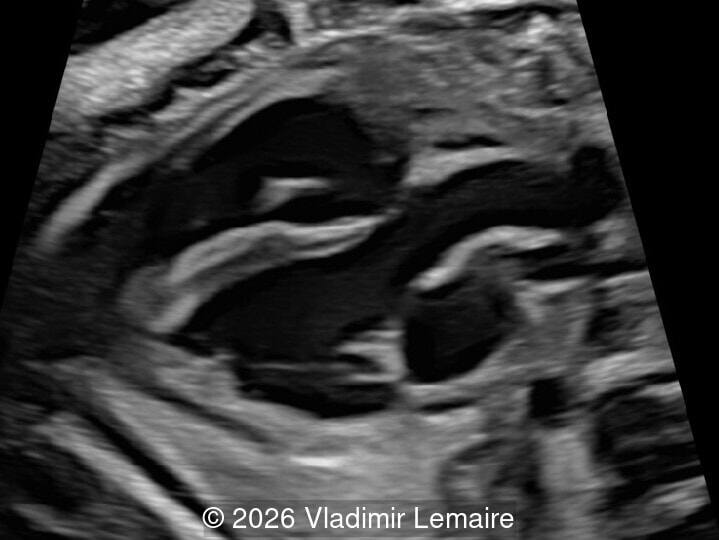

Axial plane of the fetal chest at the level of the four-chamber view.

Image 2 Axial plane of the fetal chest at the level of the four-chamber view.